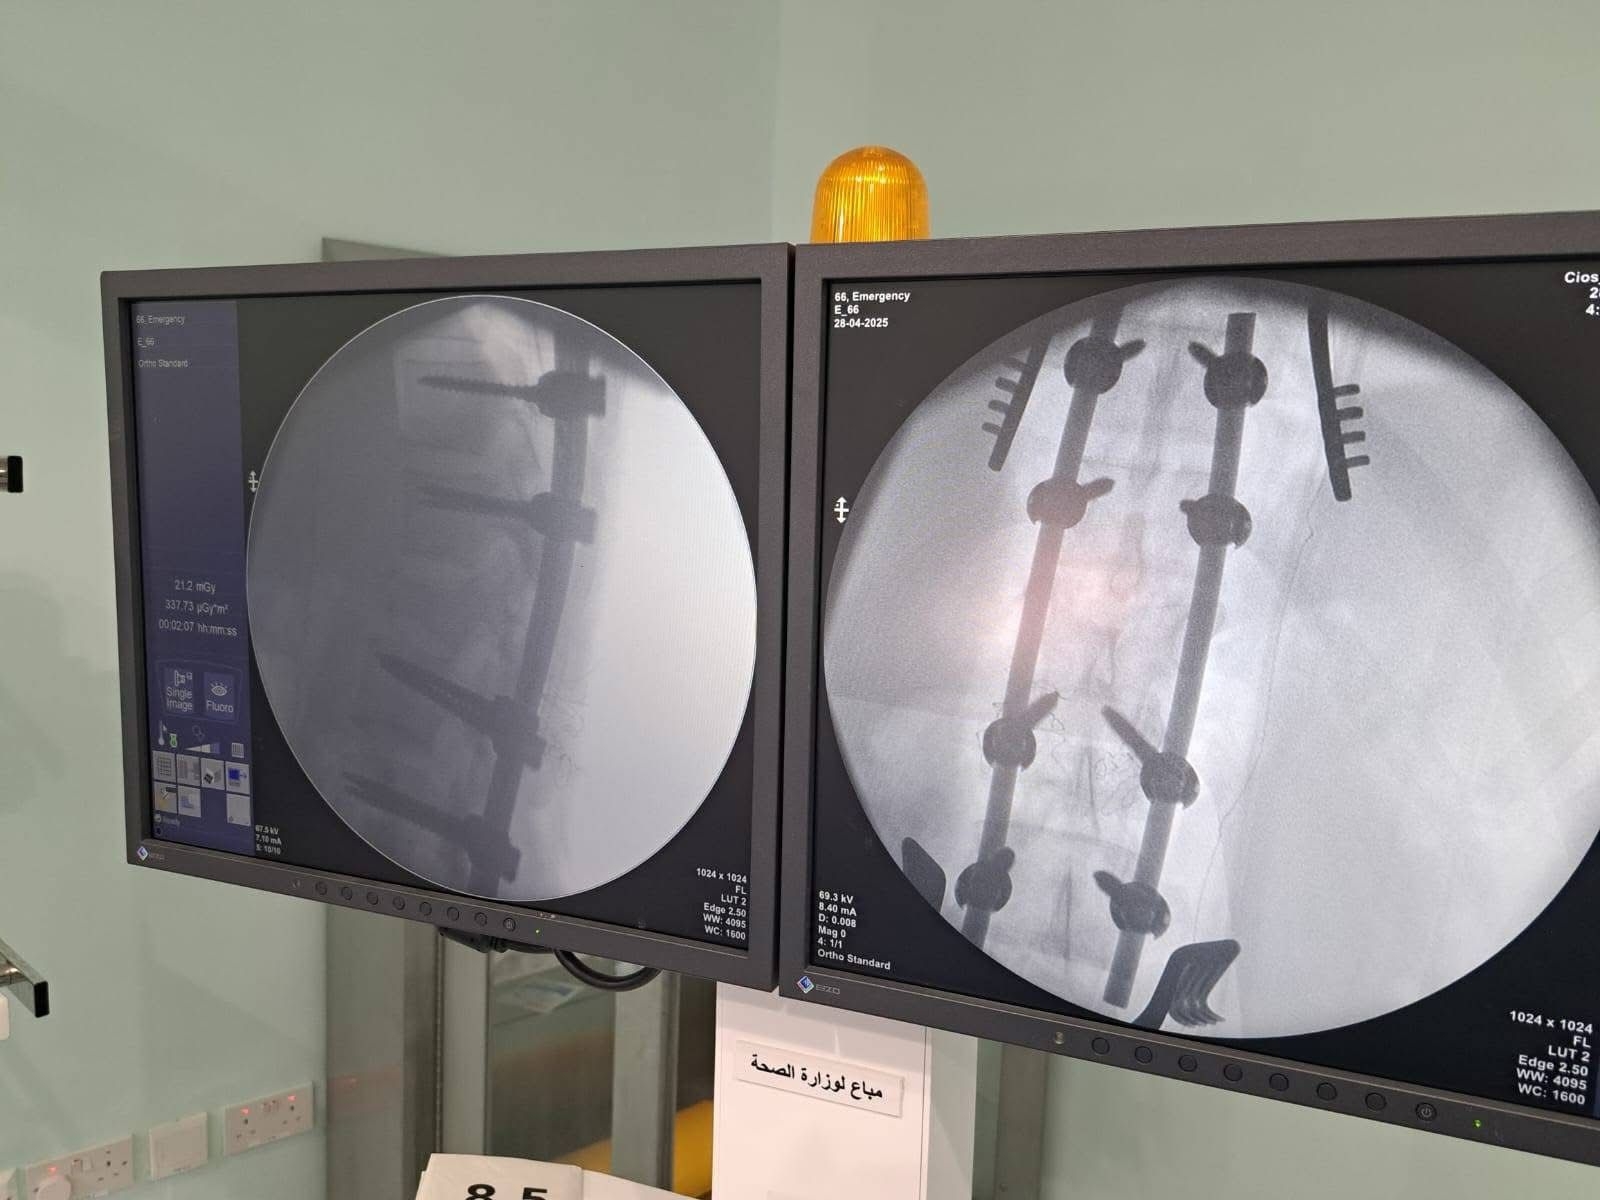

الكرك - تكللت بالنجاح عملية تثبيت للعمود الفقري وتحرير النخاع الشوكي أجريت لمريضة تبلغ من العمر 20 عامًا، في مستشفى الكرك الحكومي.

وكانت المريضة تعاني من كسر غير مستقر في الفقرة القطنية الأولى، مصحوبًا بضغط على النخاع الشوكي.